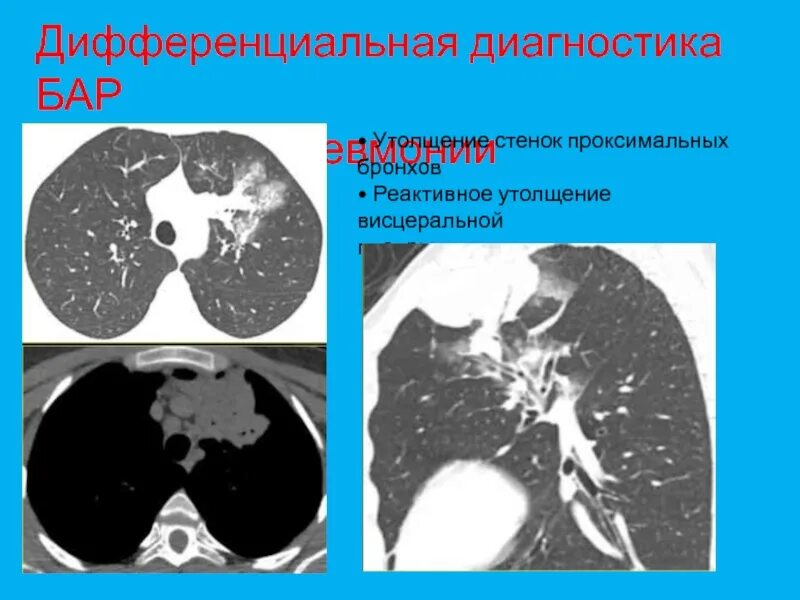

Утолщение бронха